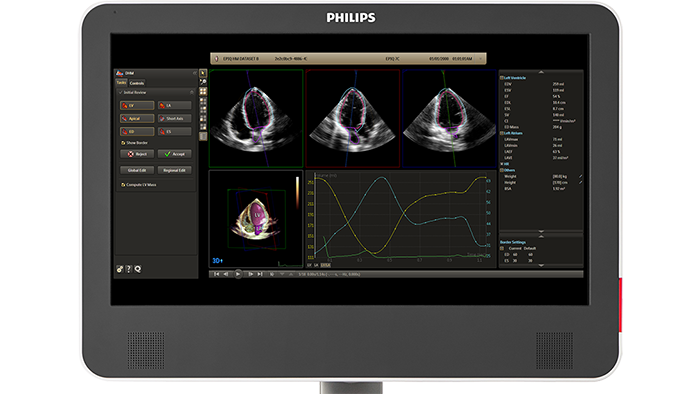

Discover the latest technology in the field of cardiovascular (or cardiac) ultrasound through Philips HeartModel 3D capabilities, which allows for cardiac 3D chamber quantifications, driven by advanced automation. Here you can find the most updated information on Philips EPIQ machines, HeartModel, as well as insights into this technology's practical application and the benefits this tool will add to your every-day cardiovascular ultrasound workflow.

Evolving from Philips HeartModel, Dynamic HeartModel provides more critical capabilities in addition to LV and LA volumes to expand your clinical use and increase diagnostic confidence through 3D echocardiography technology. The Dynamic HeartModel tracks every frame over the cardiac cycle using 3D speckle technology. The moving contours of LA and LV borders and waveforms, additional LV, LA indexes and LV mass measurements provide a holistic view of the left heart function. The LV wall motion and the linkage between the LV and LA volume change over the heart cycle in order to increase your diagnostic confidence. In addition, the multi-beat selection and results average make the heart function evaluation more reliable than single beat, being ideal for arrhythmia or atrial fibrillation patients.

Boost your confidence in cardiac quantification during everyday workflows with HeartModel. This intuitive and validated 3D tool provides robust, reproducible ejection fraction (EF) in just seconds. What’s more, HeartModel is the only validated tool to provide simultaneous LV and LA volumes. It helps you easily characterize LA volume – shown to be an indicator of cardiovascular outcomes – to yield additional clinical information with no extra time or steps.